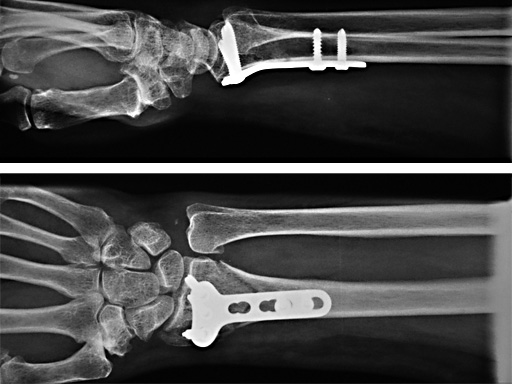

2.4 mm LCP Distal Radius Plate

The best compromise was to conduct an observational study where the treatment decision remains in the hand of the surgeons. This design allows documentation of the range of indications for treatment with the LCP, and both clinical and radiological outcomes, after plating of the distal radius. By collecting data from a large number of cases, we will identify different cohorts (e.g. patients treated with different plates) that will be compared.

A schematic overview of the LCP 3.5 mm and 2.4mm study, combined with the retrospective study is shown in the figure below. The same inclusion and exclusion criteria, as well as clinical (including the Gartland and Werley, the DASH and the SF-36 scoring systems) and radiological (centrally evaluated) outcome criteria are used in the different prospective studies. While follow-up is implemented for all cases in the "Conservative" distal radius study, only plated cases are followed in the two other prospective studies.

Special attention will be given to the expected advantages of the new LCP concept as well as to maintenance of reduction, the additional use of bone grafting, and the learning curve. The studies are controlled in order allow a comparison of the LCP systems to other conventional plating systems and conservative treatment of distal radius fractures. The retrospective part of the study (documenting the situation before the introduction of the LCP system) will show whether any shift in indication from e.g. external fixator to the LCP system has occurred and in order to define a control group accordingly for future studies.